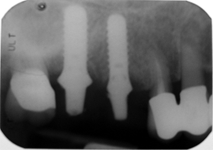

LAS Kit

Souprava pro laterální přístup k sinus liftu, speciálně navržena pro bezpečný a méně invazivní laterální přístup k nadzdvihnutí membrány sinu. LAS Kit nabízí v závislosti na anatomii dutiny ústní a plánech operace různé využití.

CAS Kit

Souprava pro krestální přístup k operaci sinus liftu tím, že se vytvoří v kosti kónický odštěpek, kterým lze membránu bezpečně nadzvednout.